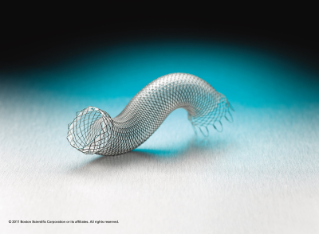

Imágenes del Stent esofágico

Examine las imágenes que desea usar en las presentaciones.